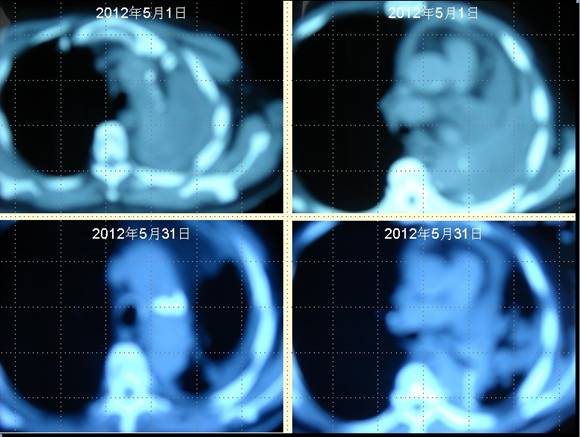

患者王某某,男,74歲,于2009年12月在濱州醫學院附屬醫院行左肺下葉占位切除術,術后病理提示為“中分化鱗狀細胞癌”侵犯支氣管壁全層,累及支氣管周圍肺組織。術后化療4個周期,局部放療30次(具體方案及劑量均不詳),2011年病灶局部復發,口服“特羅凱”“康力欣”等無效,于2012年5月1日復查肺CT示:心包積液,左側包裹性胸腔積液,后縱膈結節影,右側少量積液。經采用“中醫調胃、強腎、止血、化巖法”治療1個月,胸腔積液完全消失,心包積液明顯減少,未出現新癌灶。

肺癌王XX采用 “董氏治癌法”治療前后CT對照變化